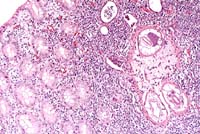

- Case 12-3. Cauda equina. The nerve bundle is replaced

by macrophages, multinucleated giant cells and a mass of neutrophils

in a necrotic area to the top left corner. The lower right shows

a mostly intact smaller nerve. 20X

AFIP Diagnosis: Cauda equina with adjacent adipose tissue:

Neuritis and ganglioneuritis, granulomatous, diffuse, severe,

with moderate chronic steatitis, Arabian horse, equine.

- Conference Note: Cauda equina syndrome is an uncommon

condition in horses in which the sacral and coccygeal nerves,

and occasionally cranial nerves V and VII, are chronically inflamed.

Resulting clinical signs include paralysis of the tail, rectum,

and bladder; anesthesia in the sacral dermatomes with a surrounding

zone of hyperesthesia; gluteal muscle atrophy; and hind limb

ataxia and weakness. In horses with cranial nerve involvement,

facial paralysis, head tilt, and masticatory muscle atrophy are

also seen.

- Marked granulomatous inflammation and proliferation of the

epineurial and perineurial sheaths are the major histopathologic

changes in the extradural nerve roots and spinal ganglia. Intradural

roots are usually less severely affected. Though some nerve fascicles

remain intact, many contain dense infiltrates of lymphocytes,

plasma cells, and macrophages extending into the fascicle interior.

Secondary to interruption of axons, retrograde chromatolysis

develops in the somatic motor neurons of the affected spinal

segments. Destruction of sensory neurons in the dorsal roots

and ganglia leads to orthograde nerve fiber degeneration in the

spinal dorsal funiculus.6